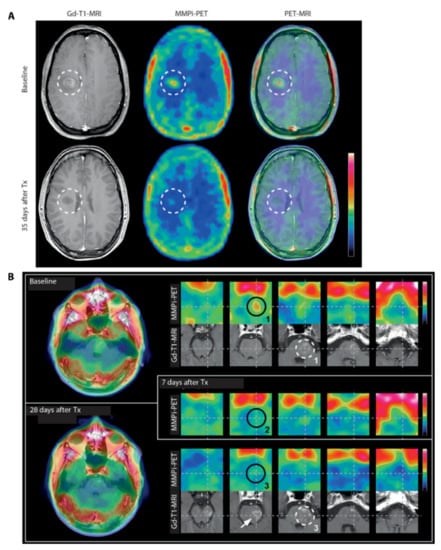

- Gerwien, H.; Hermann, S.; Zhang, X.; Korpos, E.; Song, J.; Kopka, K.; Faust, A.; Wenning, C.; Gross, C.C.; Honold, L.; et al. Imaging matrix metalloproteinase activity in multiple sclerosis as a specific marker of leukocyte penetration of the blood-brain barrier. Sci. Transl. Med. 2016, 8, 364ra152. [Google Scholar] [CrossRef] [PubMed]